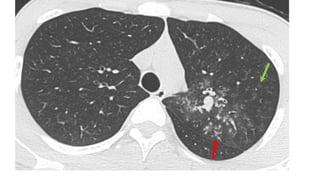

4. Chest X-ray and other relevant radiological investigations

• Chest X ray

• CT – chest (High resolution CT)